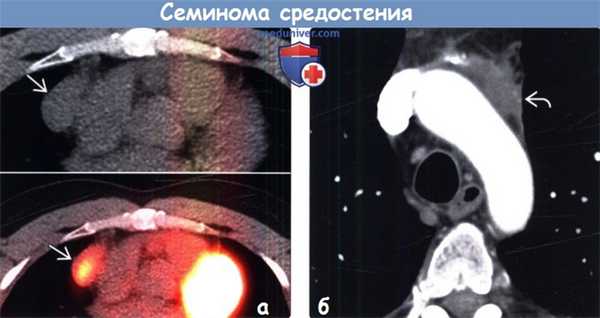

(а) Мужчина средних лет с жалобами на боли в груди. При рентгенографии органов грудной клетки в ПП проекции в левой половине переднего средостения определяется объемное образование с дольчатым контуром. На фоне образования визуализируется дуга аорты.

(б) У этого же пациента при КТ с контрастным усилением в преваскулярном отделе средостения выявляется объемное образование относительно гомогенной структуры с дольчатым контуром, локализующееся по обе стороны от срединной линии. Данное образование умеренно накапливает контрастное вещество. Медиастинальная семинома может имитировать конгломераты лимфатических узлов средостения при ходжкинской или неходжкинской лимфоме. (а) У мужчины 30 лет на совмещенных изображениях при нативной КТ (вверху) и ФДГ-ПЭТ/КТ (внизу) в правой половине преваскулярного отдела средостения определяется объемное образование, интенсивно поглощающее ФДГ. При биопсии под контролем КТ была подтверждена медиастинальная семинома.

(а) У мужчины 30 лет на совмещенных изображениях при нативной КТ (вверху) и ФДГ-ПЭТ/КТ (внизу) в правой половине преваскулярного отдела средостения определяется объемное образование, интенсивно поглощающее ФДГ. При биопсии под контролем КТ была подтверждена медиастинальная семинома.

(б) Мужчина 42 лет через четыре года после проведения химиотерапии по поводу медиастинальной семиномы. При КТ с контрастным усилением визуализируется отсутствие роста и контрастирования мягких тканей. При ПЭТ/КТ признаки метаболической активности также не были выявлены. После химиотерапии или лучевой терапии по поводу семиномы часто наблюдается резидуальная мягкотканная структура.